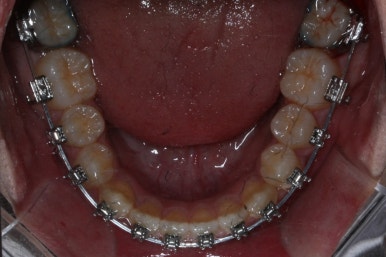

위 사진들은 부산주걱턱교정 키다리아저씨치과에 내원하셨을 당시의 입안 모습입니다.

입 안의 모습에서도 주걱턱의 특징으로는

하악이 앞으로 나와있습니다.

윗니는 뻐드러지고 아래 앞니는 뒤쪽으로 쓰러져 있습니다.

교합이 맞지 않습니다.